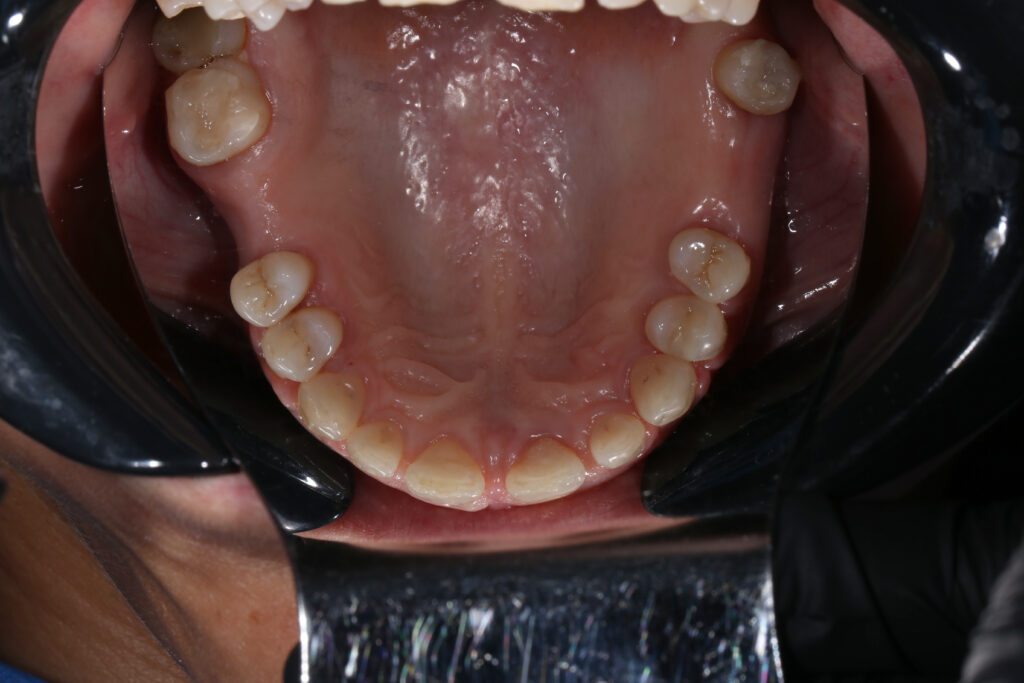

Ситуация до лечения